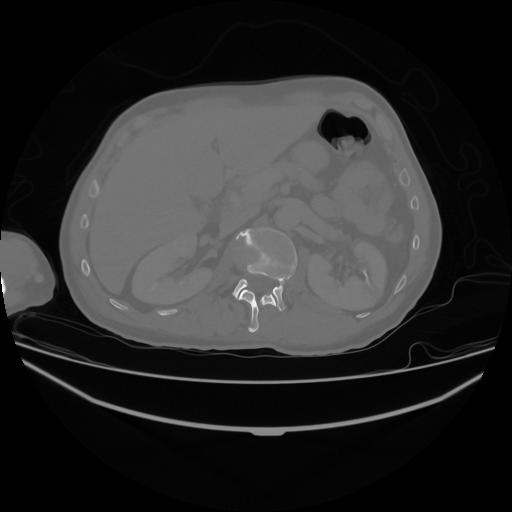

5 CUERPO,CE,Vol,1.0,CUERPO,,